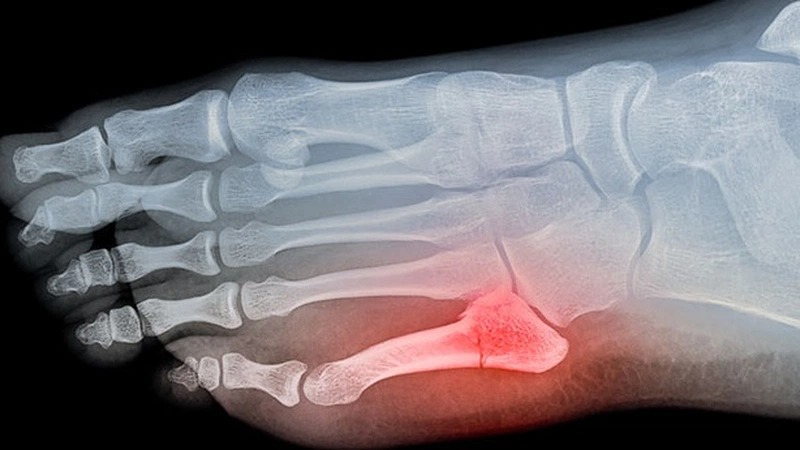

Để chẩn đoán và điều trị trật khớp ngón chân út, người bệnh cần tìm đến một bác sĩ chuyên khoa phẫu thuật xương khớp. Thông thường, việc chẩn đoán sẽ bao gồm kiểm tra vùng bị tổn thương, chụp X-quang, và có thể cần thêm các xét nghiệm hình ảnh khác như MRI để đánh giá tổn thương chi tiết hơn.

Đi khám và chụp X - quang: Trong trường hợp bạn cảm thấy đau và sưng nhiều, đặc biệt sau một chấn thương ngón chân út, quá trình đầu tiên cần làm là tới bệnh viện hoặc phòng khám để kiểm tra và đánh giá tình trạng của khớp và xương. Bác sĩ có thể yêu cầu bạn chụp X-quang để loại trừ tổn thương xương.